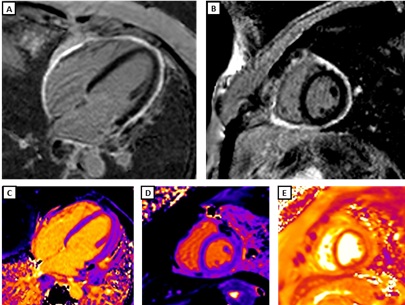

Figure 2. CMR findings at 3-month follow-up. Compared with the initial study, there is persistent pericardial enhancement on PSIR sequences 10 minutes after gadolinium infusion: A) four-chamber view and B) mid-ventricular short-axis view. Partial improvement is observed in pericardial mapping values — T1 mapping (1000 ms): C) four-chamber view and D) mid-ventricular short-axis view; T2 mapping (60 ms): E) mid-ventricular short-axis view. Findings are consistent with chronic constrictive pericarditis with residual inflammation.